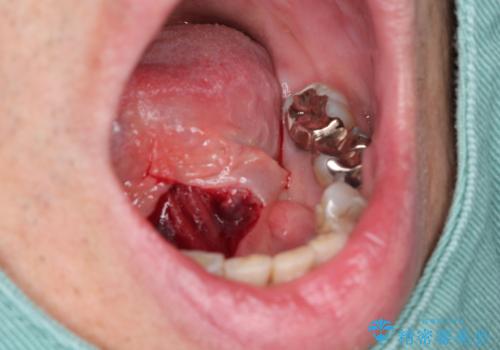

舌小帯形成術を行うことで、滑舌の改善を図ります。形成術は約5分程度で終了し、1週間後に抜糸を行い治療は終了となります。

術後、舌の動きが改善され滑舌の改善を実感することができました。

- 外科手術のため、術後に出血、痛みや腫れ、違和感を伴います